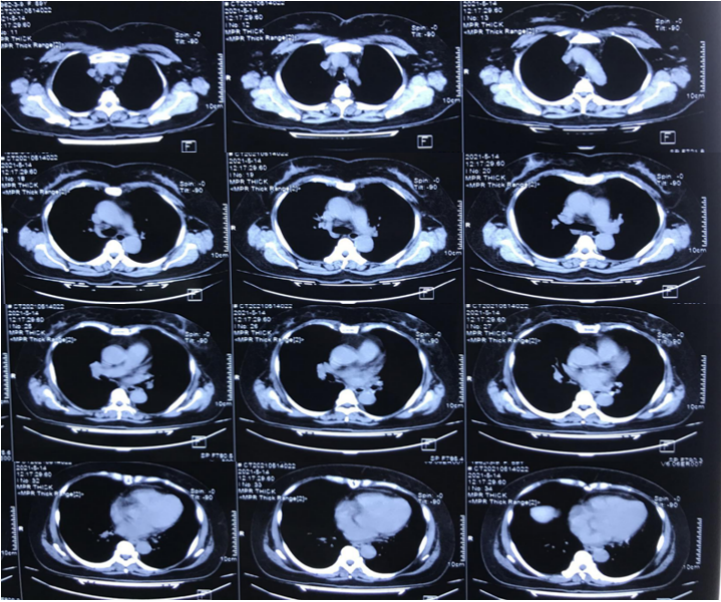

5月28日(D9)CT肺动脉造影(CTPA):肺动脉未见明显血栓形成,左肺舌段实变较重。考虑是左肺通气不良、V/Q比例失调导致氧合下降。全麻下气管镜检查发现左主支气管、左上下叶及各段管腔内均可见陈旧性血迹,充分吸除,舌段仍有残留陈旧性出血,上舌段开口见新生物(图5)

图片

图5  复查气管镜(2021-05-28)